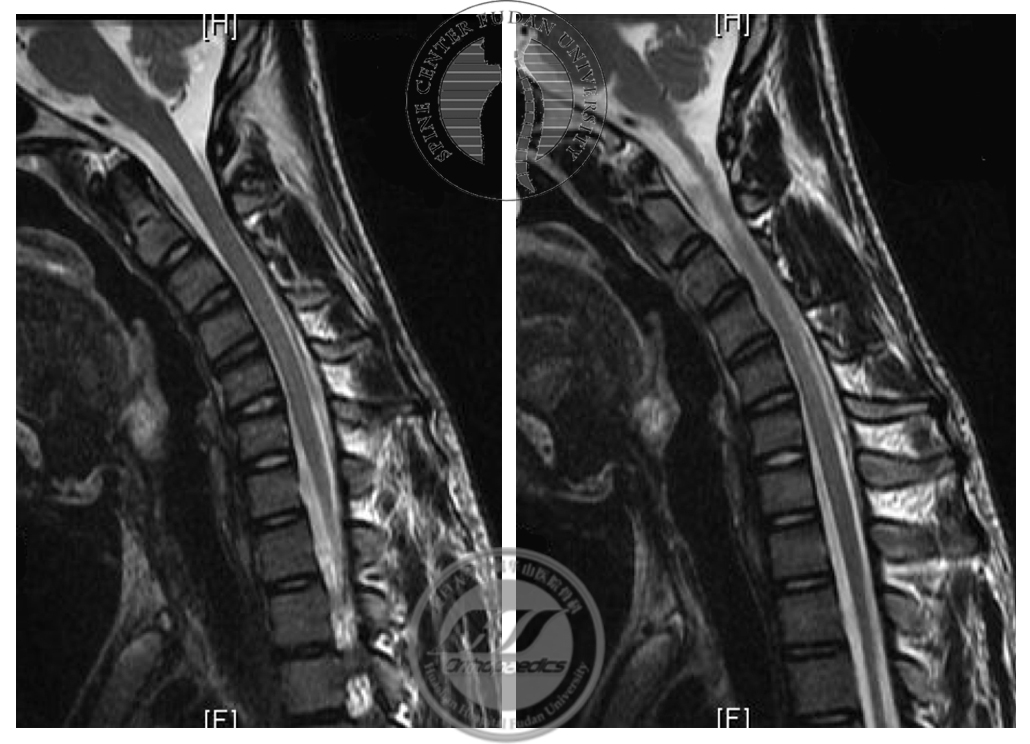

图4 屈颈位MRI T2加权像显示,硬膜囊后壁与椎管后壁分离,呈“膜-壁分离”现象;未见明显髓内信号改变

图7 术前与术后2年屈颈位MRI对比,术后T2加权像显示“膜-壁分离”现象消失